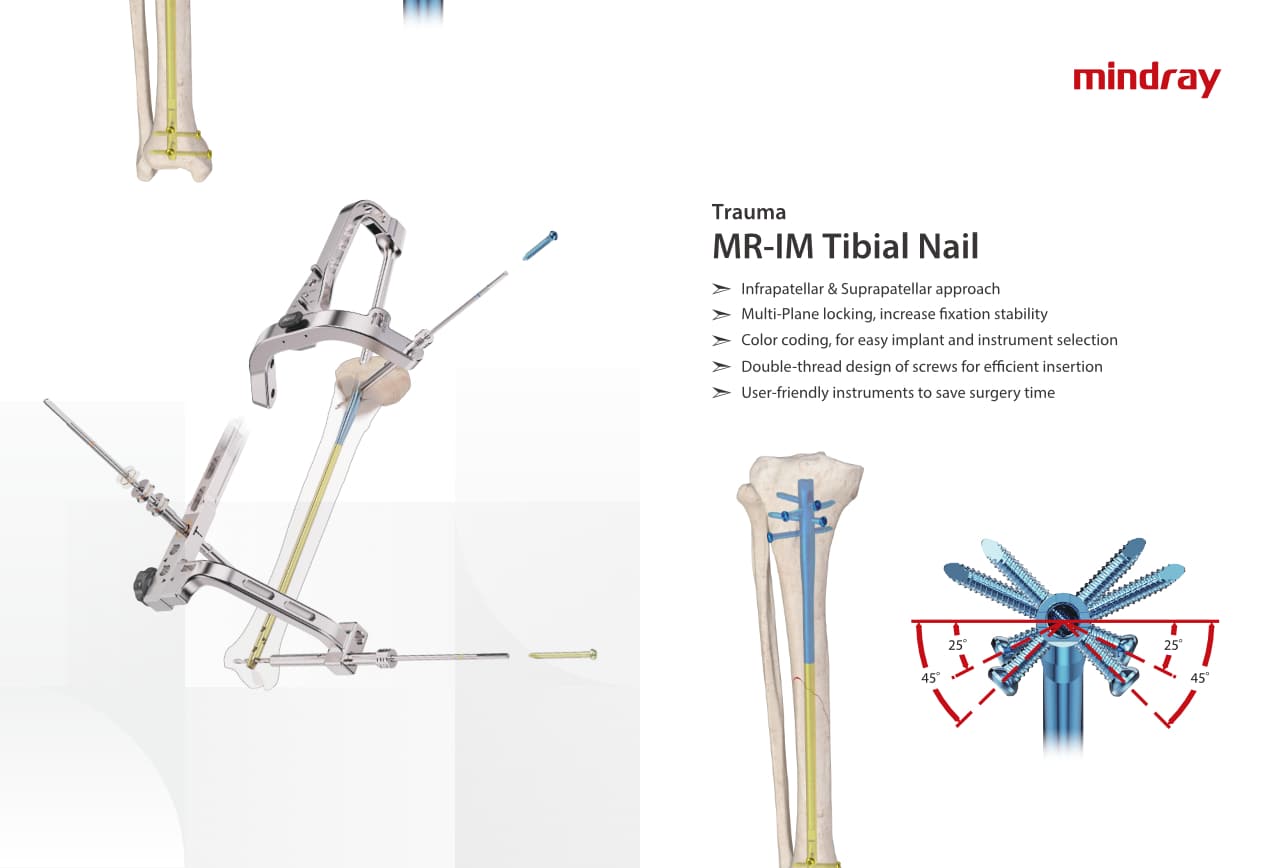

РһСҖСӮРҫРҝРөРҙРёСҮРөСҒРәРҫРө РҝРҫРҙСҖазРҙРөР»РөРҪРёРө РәРҫРјРҝР°РҪРёРё Mindray, СҖР°СҒРҝРҫР»РҫР¶РөРҪРҪРҫРө РІ РЈС…Р°РҪРө, СҸРІР»СҸРөСӮСҒСҸ РҫРҙРҪРёРј РёР· РІРөРҙСғСүРёС… РҝСҖРҫРёР·РІРҫРҙРёСӮРөР»РөР№ РҫСҖСӮРҫРҝРөРҙРёСҮРөСҒРәРҫР№ РҝСҖРҫРҙСғРәСҶРёРё РёР· РҡРёСӮР°СҸ. РһРҪРҫ Р·Р°РҪРёРјР°РөСӮСҒСҸ РёСҒСҒР»РөРҙРҫРІР°РҪРёСҸРјРё Рё СҖазСҖР°РұРҫСӮРәРҫР№, РҝСҖРҫРёР·РІРҫРҙСҒСӮРІРҫРј Рё РјР°СҖРәРөСӮРёРҪРіРҫРј СӮСҖавмаСӮРҫР»РҫРіРёСҮРөСҒРәРёС… Рё СҒРҝРёРҪалСҢРҪСӢС… РёР·РҙРөлий, РҝСҖРҫРҙСғРәСҶРёРё РҙР»СҸ Р°СҖСӮСҖРҫРҝлаСҒСӮРёРәРё Рё РҙСҖСғРіРёС… С…РёСҖСғСҖРіРёСҮРөСҒРәРёС… РёР·РҙРөлий. РЎ РјРҫРјРөРҪСӮР° СҒРІРҫРөРіРҫ РҫСҒРҪРҫРІР°РҪРёСҸ РІ 1999 РіРҫРҙСғ РјСӢ СғСҒРҝРөСҲРҪРҫ РҝСҖРҫСҲли СҒРөСҖСӮифиРәР°СҶРёСҺ ISO 9001, ISO 13485 Рё CE, РІСӢРҙР°РҪРҪСғСҺ T?V Рё СҚРәСҒРҝРҫСҖСӮРёСҖСғРөРј РҝСҖРҫРҙСғРәСҶРёСҺ РІ РұРҫР»РөРө СҮРөРј 50 СҒСӮСҖР°РҪ РҝРҫ РІСҒРөРјСғ РјРёСҖСғ.